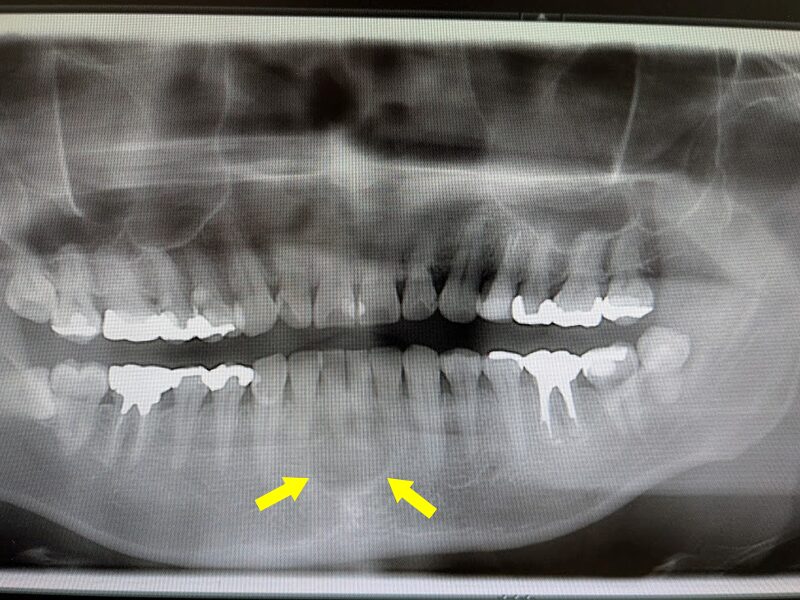

下顎前歯部の歯根嚢胞

下顎前歯部の歯根嚢胞の患者様です。かかりつけの歯科医院から口腔外科の受診を勧められ、インターネットで口腔外科を検索し、当院を受診されたとのことでした。下顎前歯部に歯根嚢胞を認める患者様です。

初診時は、下顎前歯部には根管治療が未実施で、頬側の歯肉に膿瘍を形成しておりました。患者様に状態を説明し、根管治療の後、外科的歯根端切除術および嚢胞摘出術を行う治療計画を説明しました。

下顎前歯1番(中切歯)の歯根の先端部に透過像を認めます。

初診時のCT画像所見です。下顎前歯部の骨が大きく吸収していることが分かります。